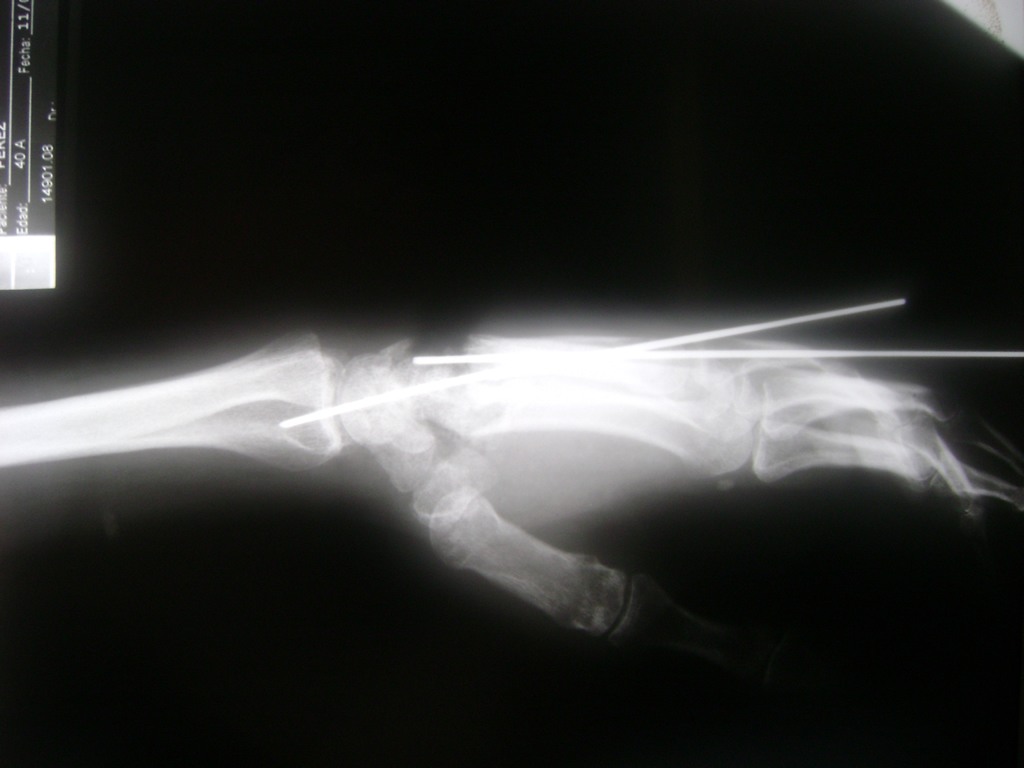

Cirugias en El Salvador - Cirugías de Muñecas y Manos

Los procedimientos más comunes en cirugía de la mano son aquellos destinados a reparar traumatismos, incluyendo lesiones de tendones, nervios, vasos sanguíneos, y articulaciones; huesos fracturados; y quemaduras, cortes, y otros daños de la piel.